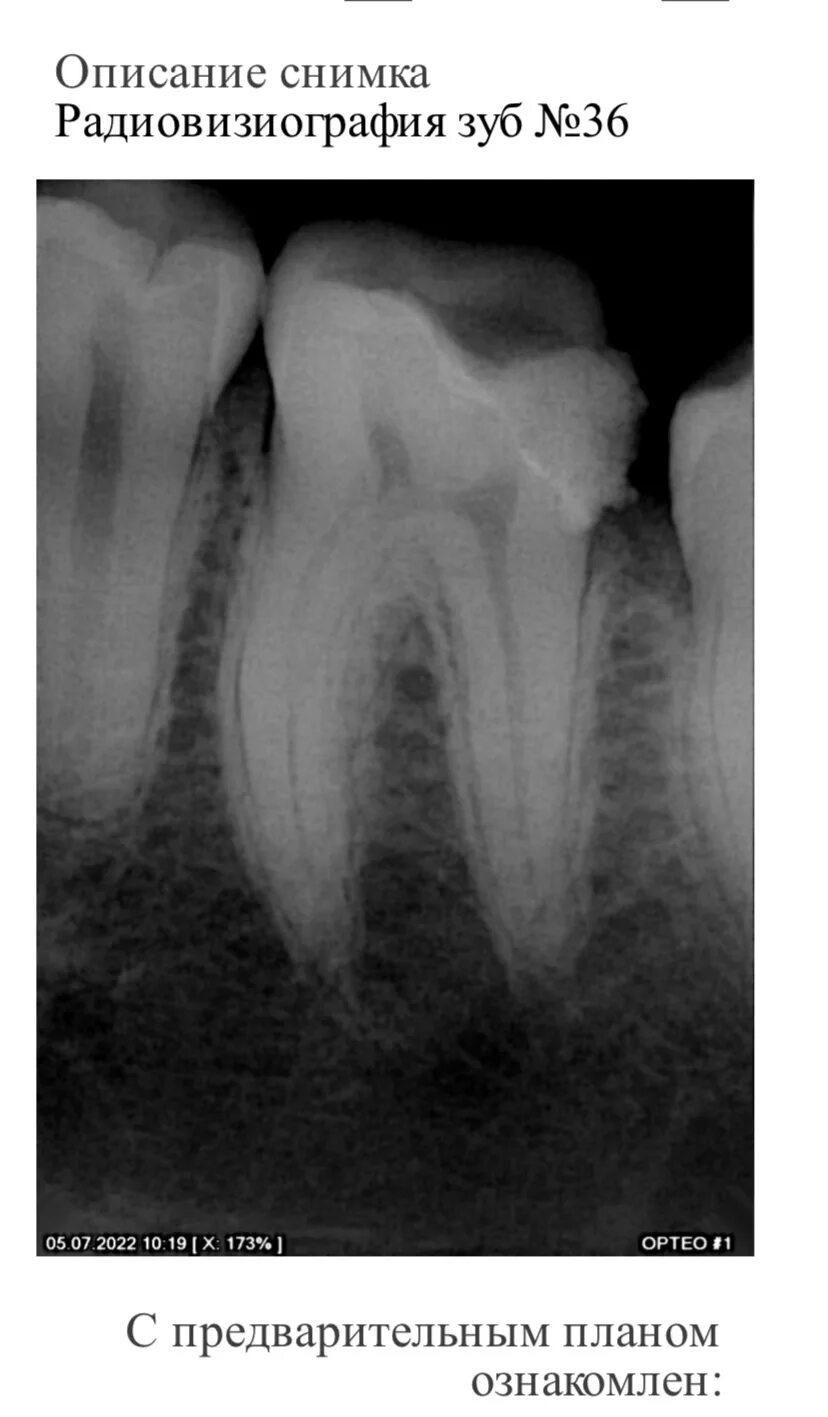

Как понять снимок зуба